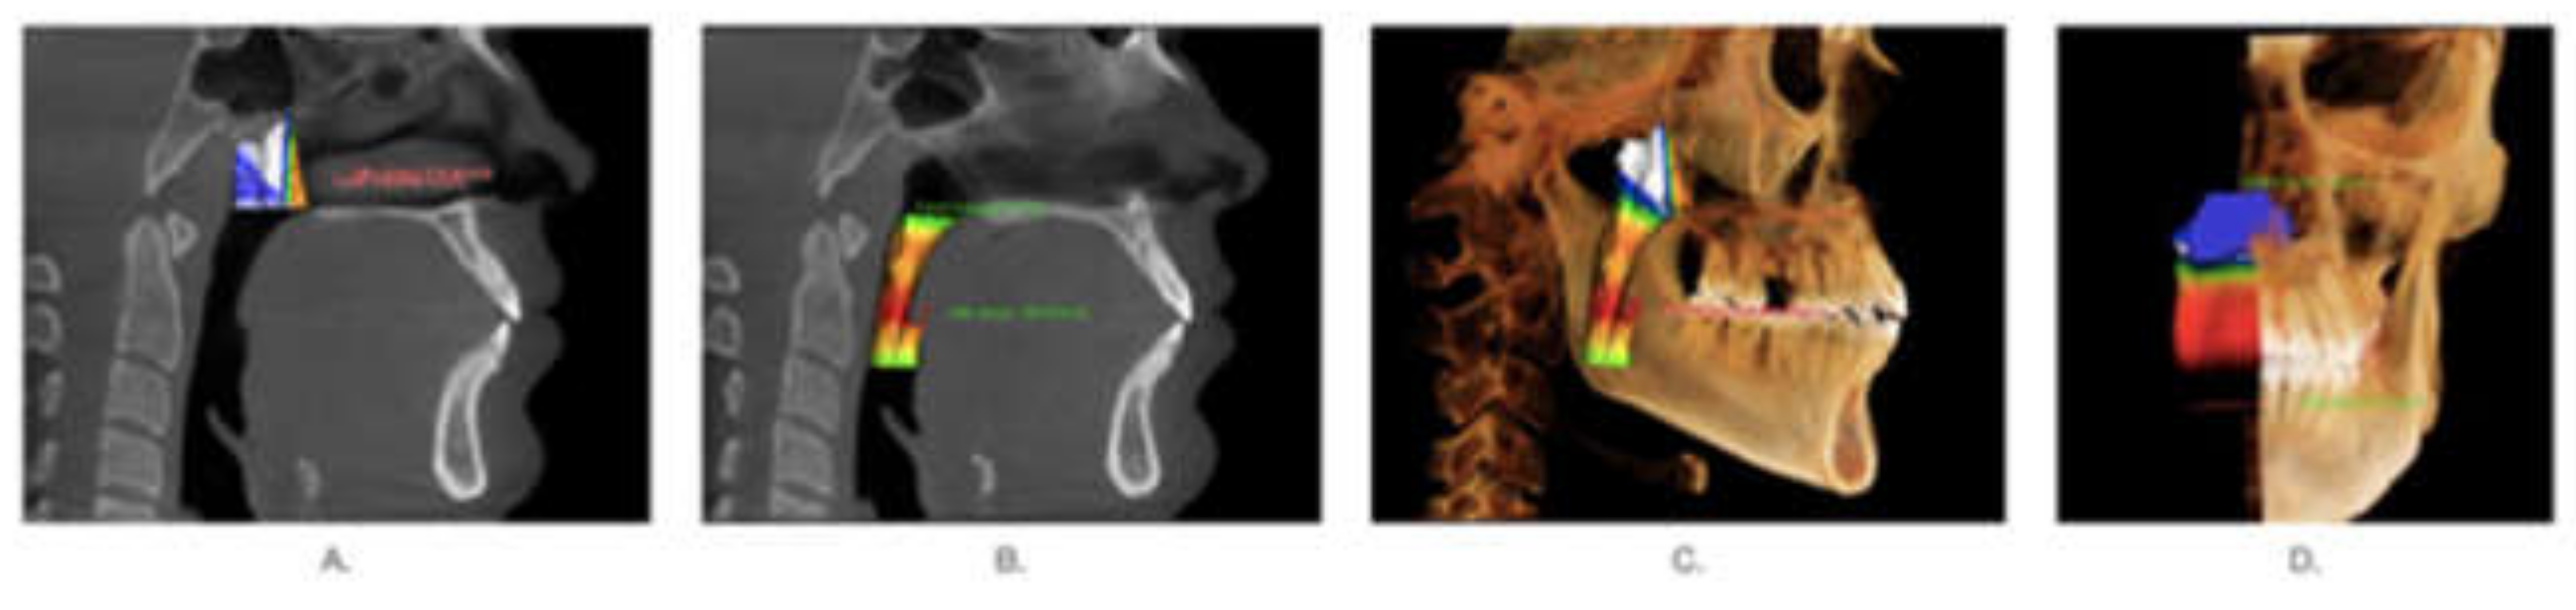

2. Methods